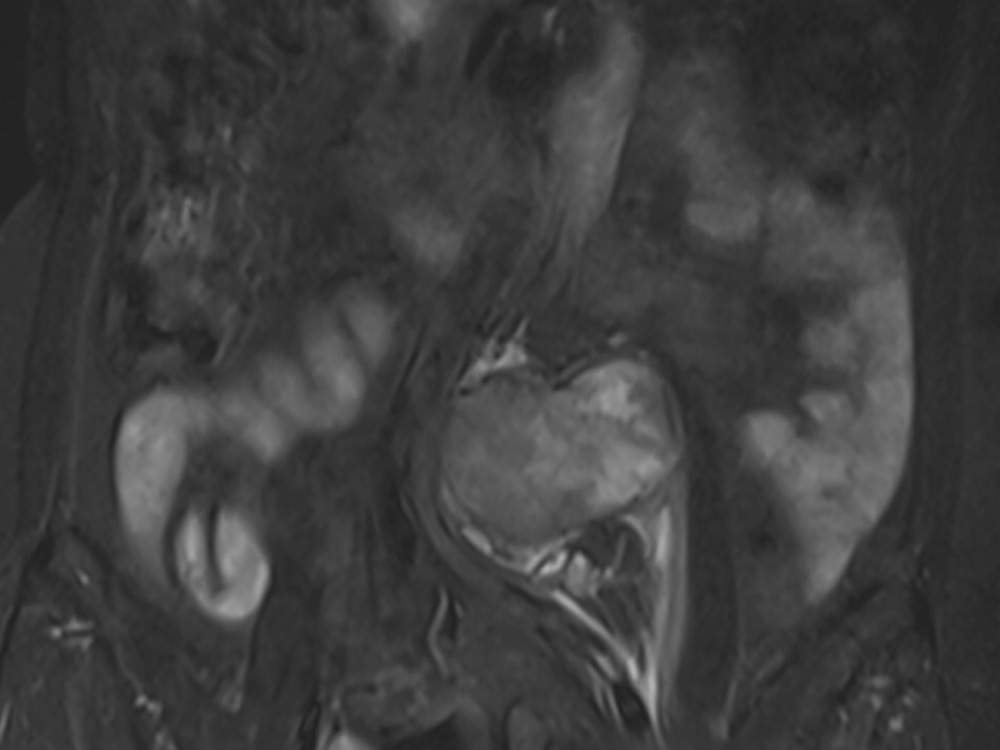

E. Dion 06/11/2019